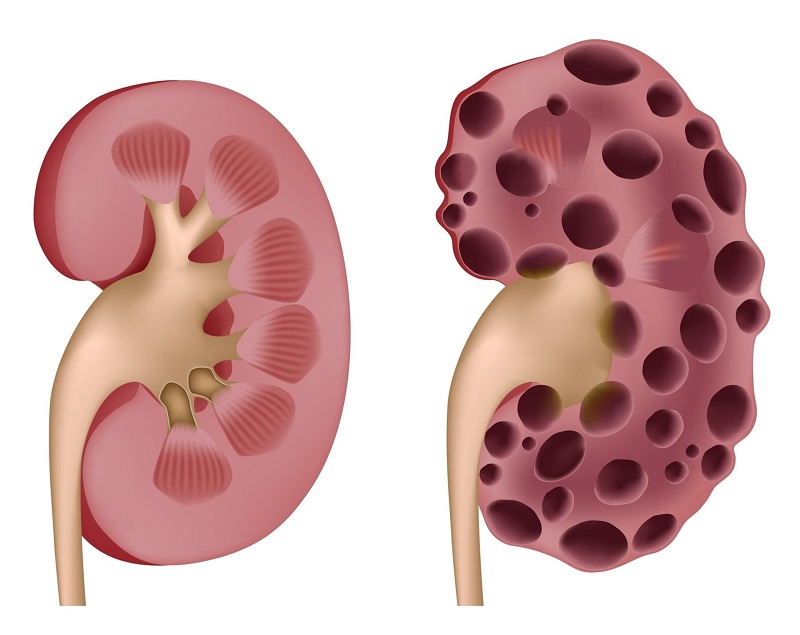

کیستهای کلیه بهصورت کیسههای کوچک و دیواره نازکی هستند که با مایع پر شدهاند. با افزایش سن و یا به علت بیماری، کیستها ممکن است در سطح کلیه یا در جداره نفرونها ایجاد شوند. اندازه آنها میتواند از یک نخود تا یک گریپفروت متغیر باشد. بعضی از این کیستها در طول زمان به رشد خود ادامه میدهند اما بعضی دیگر اندازه ثابتی دارند.

دو نوع کیست کلیه وجود دارد که شامل کیستهای ساده و کیستهایی که در بیماری پلیکیستیک بروز میکنند. کیستهای ساده اغلب بر روی کلیهها و گاهی در لولههای نفرون ایجاد میشوند، دیواره نازکی دارند و حاوی مایعی آبکی هستند. این نوع کیستهای به کلیهها آسیب نمیزنند و بر عملکرد آنها تأثیر منفی نمیگذارند. اما در مقابل، بیماری کلیه پلی کیستیک (PKD) یک بیماری ارثی است که باعث ایجاد کیستهای متعدد بر روی کلیه یا درون نفرونها میشود. کیستهای PKD پتانسیل آسیب زدن به کلیه را دارند و حذف آنها مستلزم انجام اقدامات درمانی و مراقبتی است.